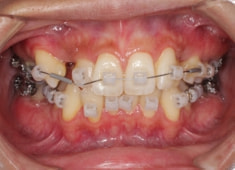

治療開始時